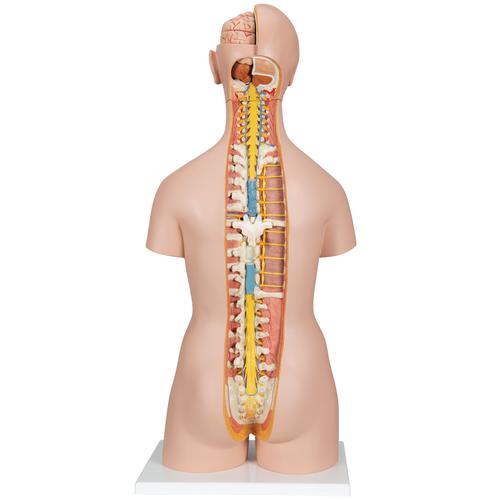

This meticulously crafted torso is expertly hand-painted with precision and made from high-quality plastic. All 3B torsos are designed and produced in Germany. This unisex human torso model features a distinctive open neck and back section extending from the cerebellum to the coccyx. It accurately depicts vertebrae, intervertebral discs, spinal cord, spinal nerves, vertebral arteries, and numerous other components in this vibrant representation of human anatomy. This human torso model includes the following detachable parts and organs: